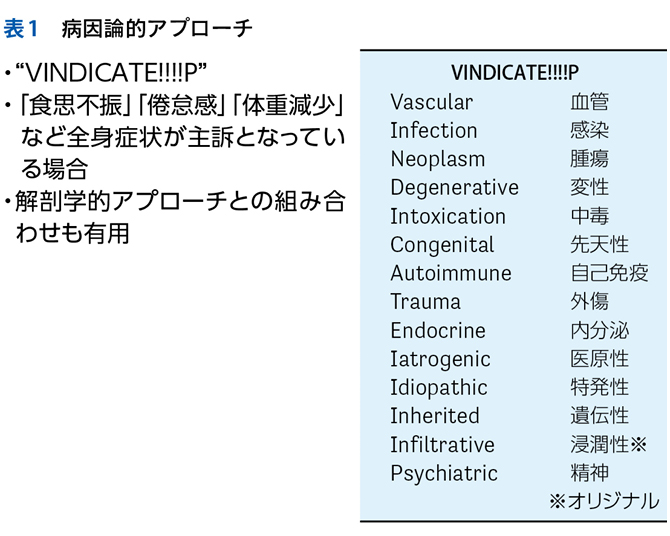

▶ 筆者の提唱する,分析的診断の「型」を図1に示した。冒頭に述べた「オリオン座を分析的に同定する手順」になぞらえ,診断推論を5つのステップにわけている。1つずつ解説しよう。